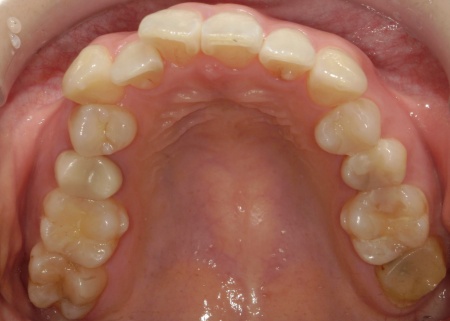

治療開始から約3ヶ月後、14枚目のアライナーの装着期間が終了したタイミングで歯並びの状態を確認しました。

確認したところ問題なく歯が動いていたため、歯に装着していたアタッチメントを取り外しています。

その後、矯正治療後の歯並びが後戻りしないようにするためのリテイナー(保定装置)の型取りを行いました。

約1週間後に完成したリテイナーをお渡しし、1日12時間ほど装着していただくようお伝えして治療を終了しました。